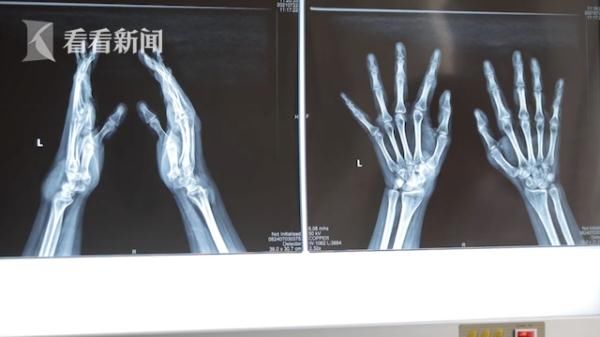

坐落于沈阳的北部战区总医院整形外科的主治医师赵海介绍道:“患者来的时候,全身左耳、双手、双足一共有15处痛风石,双手10个,脚上四个,耳朵上一个,左腕部最大的能有鸡蛋大小,手部最小的能有黄豆大小。”

而小王的行动也受到了病痛的限制。他告诉采访采访人员:“除了疼痛外,痛风对关节的行动也造成了影响,比如说回弯回不过去 一碰就疼,走路会瘸。”